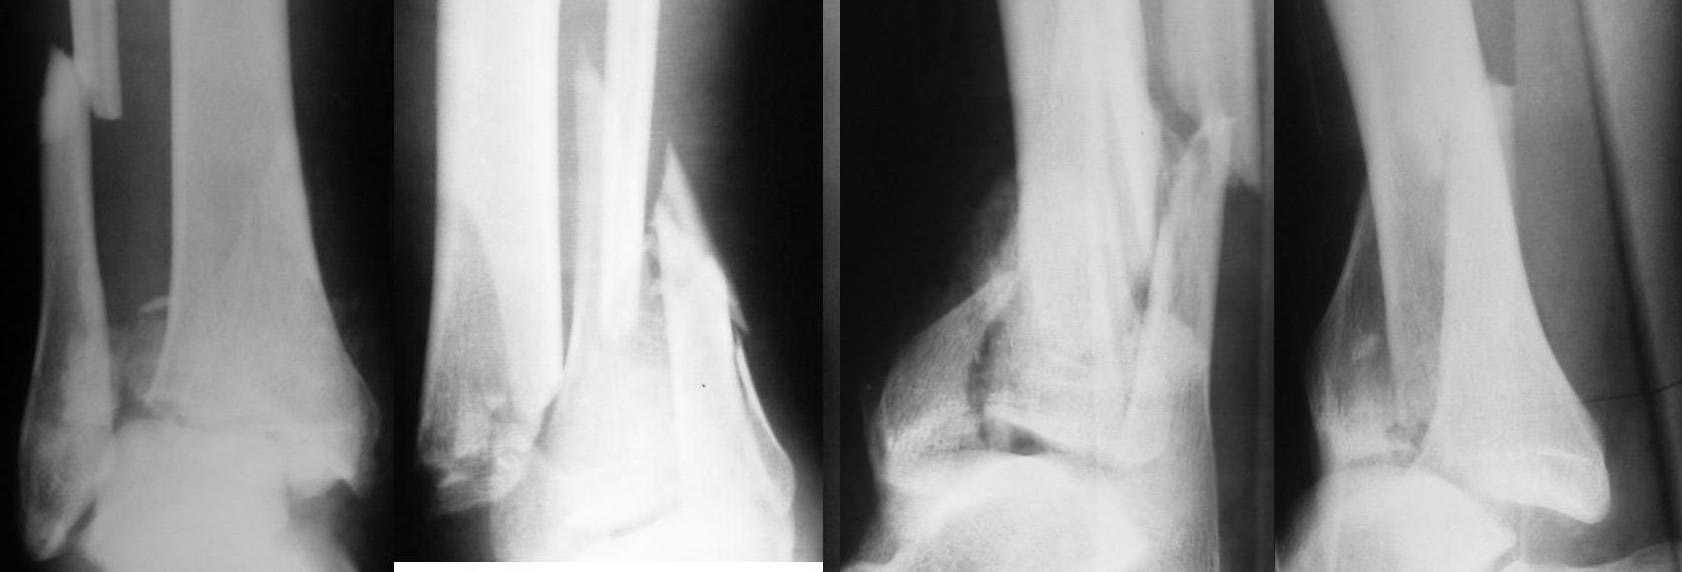

Больной 38 лет, поступил в отделение 13.01.2008г. Падение с высоты. Сложные переломы костей обеих голеней. Переломы - закрытые. Наложены гипсовые лонгеты. Какова дальнейшая тактика? Вид оперативного вмешательства?